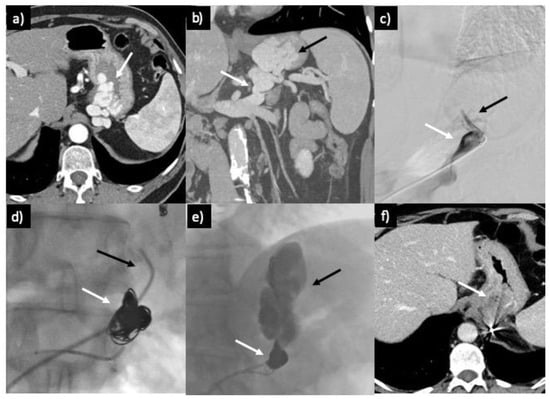

3.2. Technique

3.2.2. CARTO